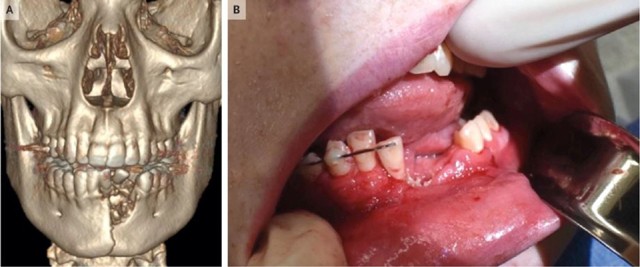

Theo báo cáo của Tạp chí Y học New England được công bố vào ngày 19/6, bệnh nhân nhập viện trong tình trạng có nhiều vết thương ở miệng, nhiều răng bị mất và hàm dưới bị gãy. Bác sĩ Katie Russell cho thiếu niên cho biết, trong quá trình điều trị, họ đã phải nhổ vài cái răng ra khỏi miệng vì chân răng vị vỡ, đồng thời đặt một tấm lưới nha khoa ở dưới nướu để ổn định xương hàm.

Nhưng sau đó miệng cậu bé vẫn không khép lại được, cuối cùng các bác sĩ đã bịt hàm bệnh nhân lại trong 6 tuần để vết thương có thời gian chữa lành.

"Khi tiếp nhận bệnh nhân, tôi không ngờ rằng một cây thuốc lá điện tử có thể nổ mạnh đến vậy. Phải mất rất nhiều lực để có thể phá vỡ xương hàm", Russell cho biết.